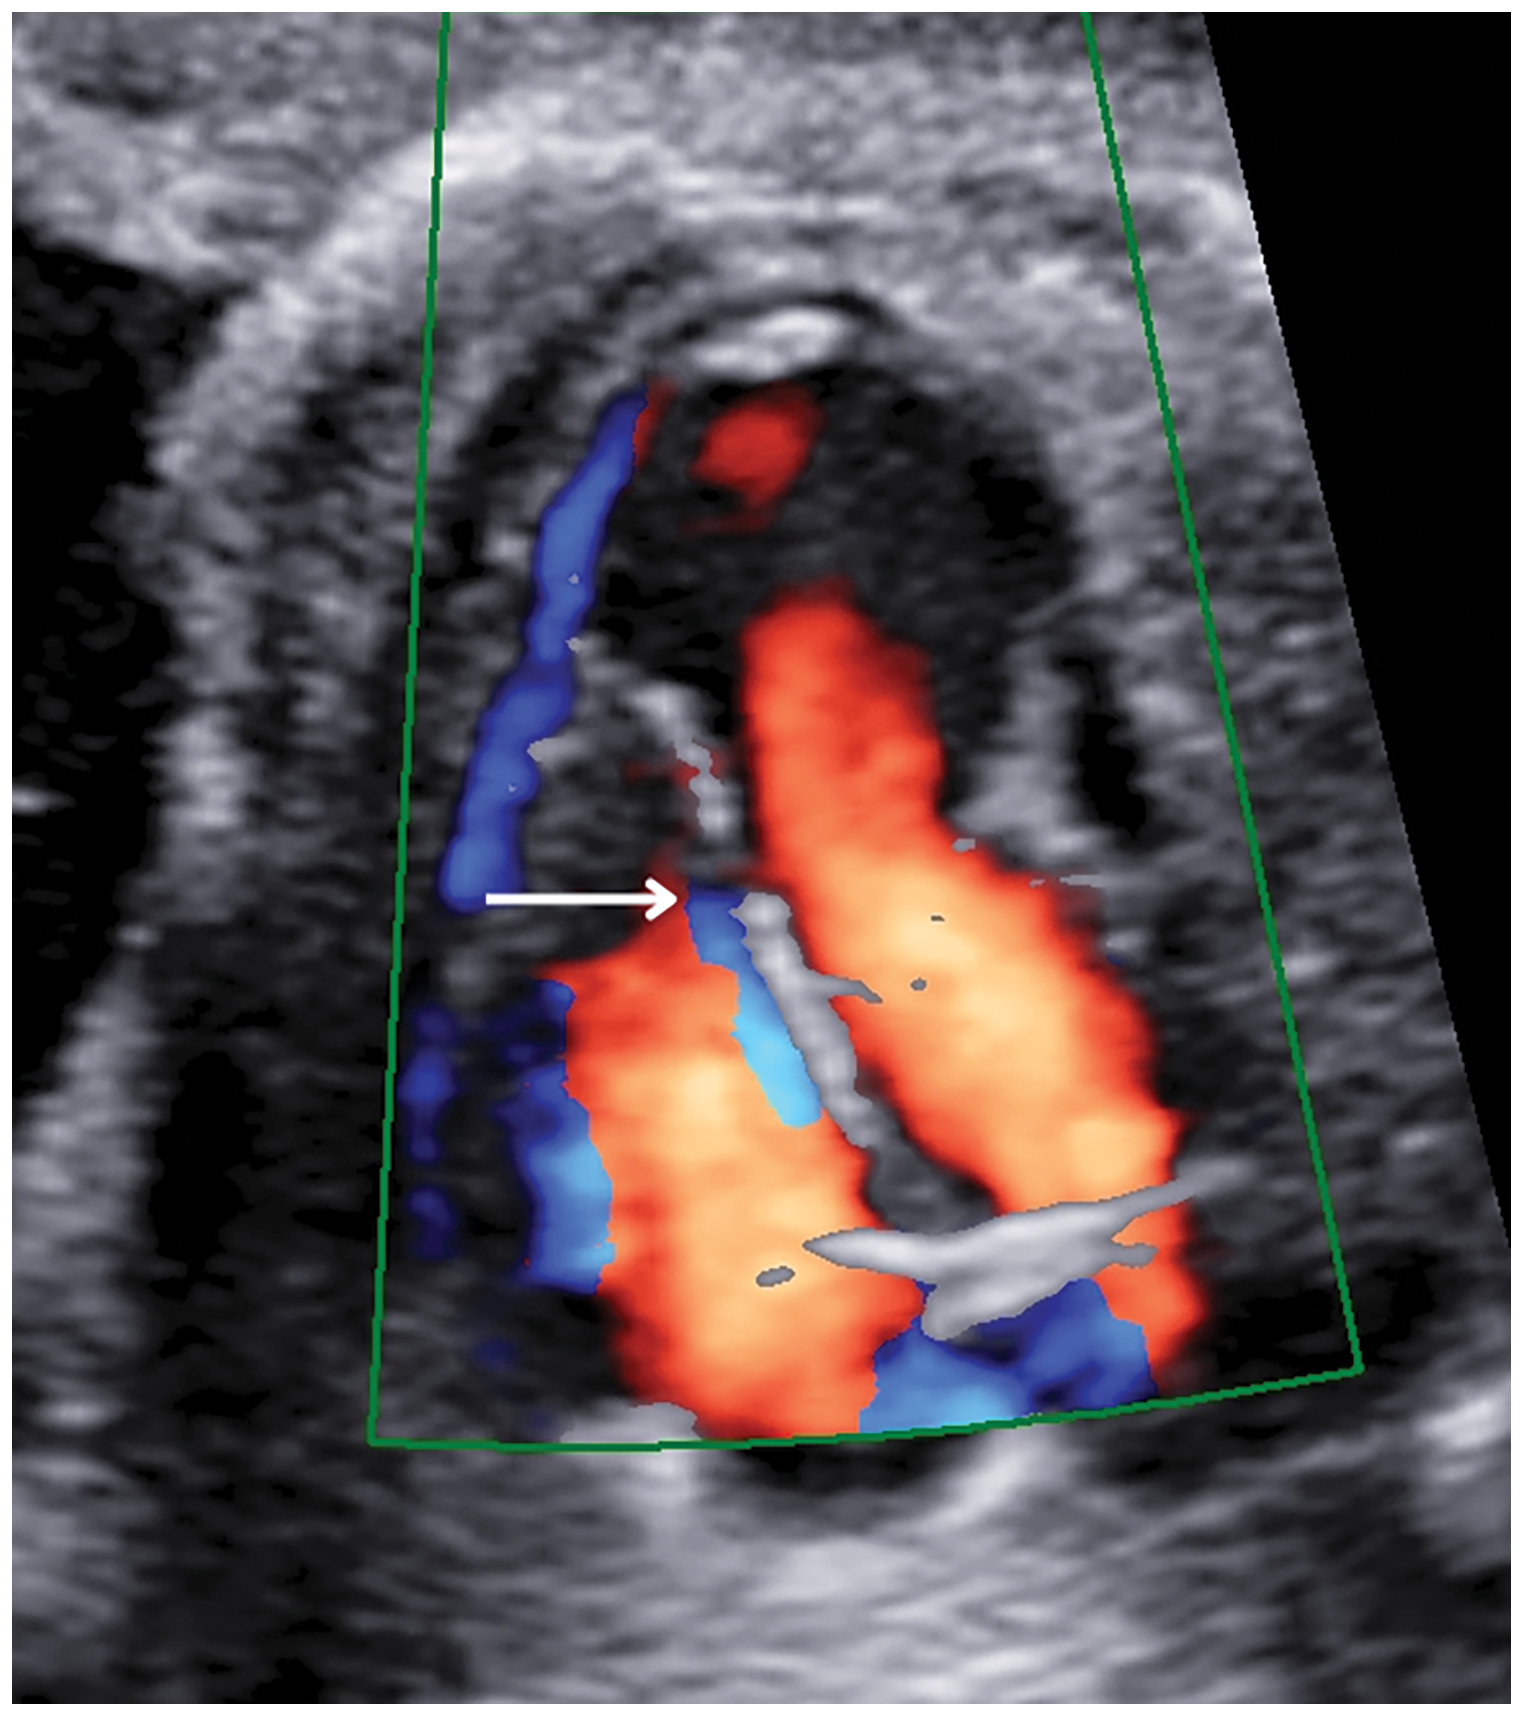

This aneurysmatic image was 11 mm × 13 mm in size, and in addition, there was a 1.79 mm muscular ventricular septal defect in the apical region of the interventricular septum (Fig. 2).

Figure 2: A four-chamber cross-section at 24 weeks of pregnancy showed a muscular ventricular septal defect (white arrow)

Color Doppler ultrasonography showed an aberrant fibrous band in the LV and turbulent flow during systole, which was thought to be related to this band (Fig. 3).

Figure 3: A color doppler ultrasound image of turbulent flow in the left ventricle at 24 weeks of gestation. LVA, left ventricular aneurysm